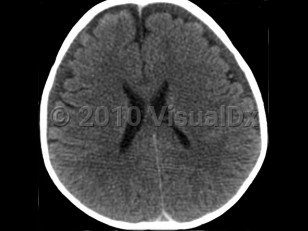

It is thought that the primary injury arises as a result of the multidirectional forces from shaking, leading to a form of whiplash injury associated with diffuse axonal injury, tearing of bridging veins, and subsequent intracranial bleeding. The secondary brain injury is due to a combination of hypoxia, ischemia, and brain edema. The end result is destruction of brain cells, a reduced supply of oxygen to brain cells, and brain swelling leading to varying degrees of neurological deterioration and occasionally death. Anatomically, the combination of a not-yet myelinated brain, a relatively heavy head upon weak neck muscles, and lack of control of the head and neck are factors that predispose babies to this form of injury.

Abusive head trauma may present with one or more of the following clinical features: subdural hemorrhage, retinal hemorrhage, and encephalopathy. Retinal hemorrhages are present in approximately 85% of cases and may be unilateral, but the diagnosis of abusive head trauma should not be excluded if they are absent.